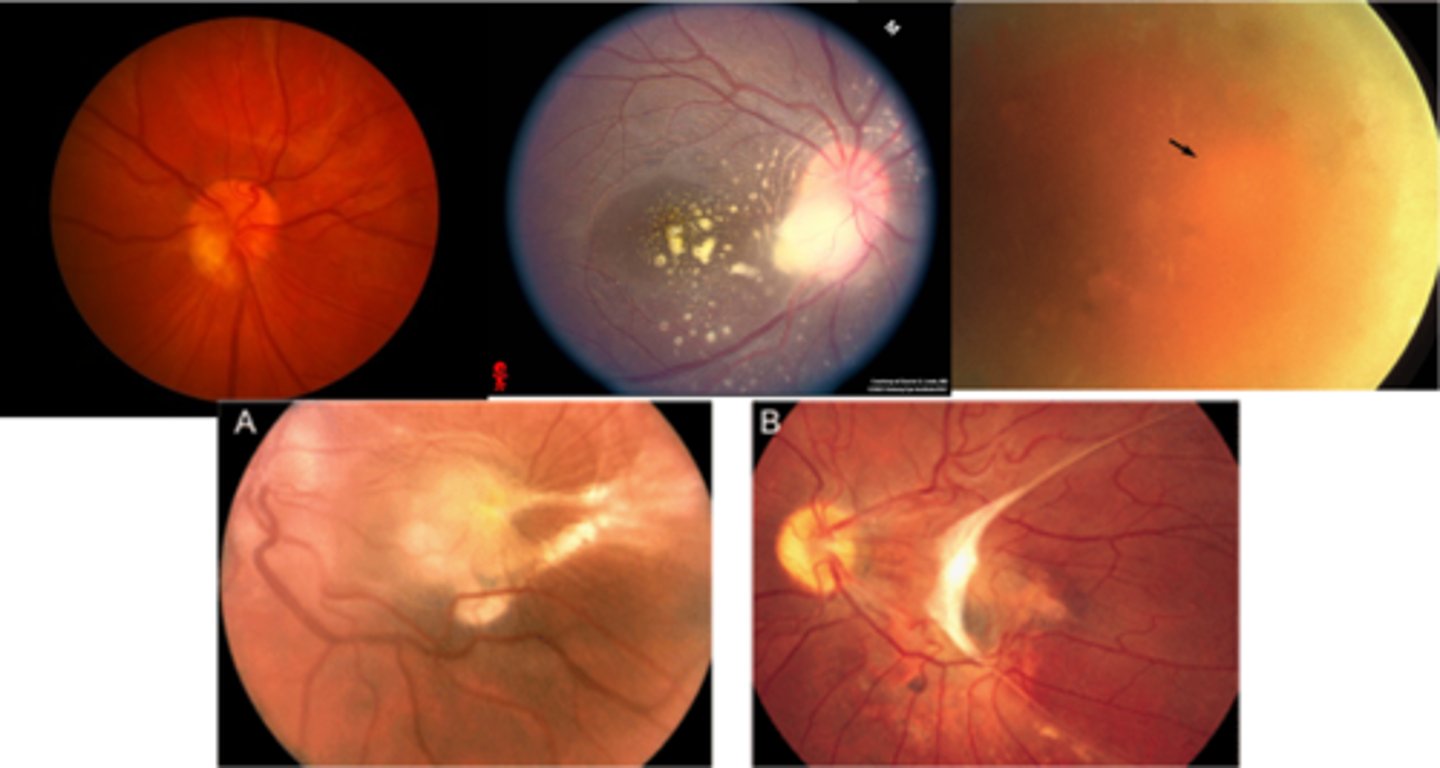

What is ocular histoplasmosis?

multifocal, bilateral chorioretinitis

What causes ocular histoplasmosis?

Histoplasma capsulatum soil fungi or mold = carried by birds or bats, esp seen in the Ohio-Mississippi River Valley = humans inhale spores in poop = affects lungs, other organs

What is the classic triad of signs in ocular histoplasmosis?

"punched-out" chorioretinal scars aka "histo spots" = outer retinal atrophy of ONL, PR's, RPE = scarring = yellow-white sclera or darker RPE hyperplasia

PPA = often further out, more irregular that crescents

absence of vitritis = white translucent dots floating in vitreous

What is ocular toxoplasmosis?

focal, full-thickness retinochoroiditis

What causes ocular toxoplasmosis?

Toxoplasma gondii protozoan parasite = carried by cats (definitive host) but also other humans, mammals, birds, or reptiles (intermediate hosts)

What are the 3 main ocular findings of ocular toxoplasmosis? Differentiate which are active vs latent.

white focal retinitis = active only

overlying vitritis = "headlight in the fog" = active only

nearby large pigmented retinochoroidal scar = active and latent

What finding of toxoplasmosis is seen in A/B?

retinitis turns into hazy scar with nerve pallor

What finding of toxoplasmosis is seen in C/D?

scarring overtime with VA loss/scotoma

What findings of toxoplasmosis are seen here?

retinal vasculitis

exudative scar

focal, hazy vitritis and retinitis

What findings of toxoplasmosis are seen here?

latent scars